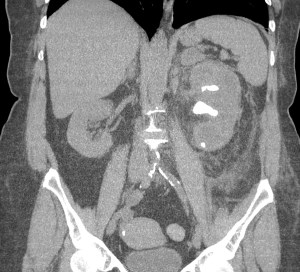

CASO 2: Paciente de 68 años con dolor en flanco izquierdo, fiebre y malestar general. A la exploración existe enrojecimiento de la piel con sensación de masa palpable y puño percusión muy positiva.

El paciente es alégrico al Iodo. Se realiza TC sin contraste para ampliar estudio.

Todos estos hallazgos están en relación con una Pielonefritis Xantunogranulomatosa que afecta al riñón derecho junto con una colección que ha fistulizado a región lumbar.

- Pielonefritis Xantunogranulomatosa.

- Es una forma infrecuente de pielonefritis crónica, de origen obstructivo, caracterizada por la formación de un absceso granulomatoso que puede extenderse al EPR-, severa destrucción renal y un cuadro clínico de fiebre, malestar general, dolor en el flanco y masa renal, a veces palpable.

- En placa simple podía verse un masa que renal con o sin borramiento de la línea del psoas. En ecografía, cálculos y aumento del tamaño renal en la forma difusa con múltiples áreas anecoicas correspondientes a las colecciones purulentas.

- Los hallazgos en TC pueden ser:

- Uni o bilateralidad de la lesión.

- Afección difusa o localizado.

- Litiasis de tipo coraliforme, calcificaciones intraparenquimatosas.

- Aumento difuso del tamaño renal.

- Áreas hipodensas o hipoecogénicas dentro de la lesión renal debidas a cálices dilatados, abscesos o áreas de necrosis parenquimatosa.

- Pobre o nula eliminación del medio de contraste en el riñón afectado.

- Compromiso inflamatorio que excede los límites del riñón y genera colecciones periféricas o extensión hacia vísceras vecinas.